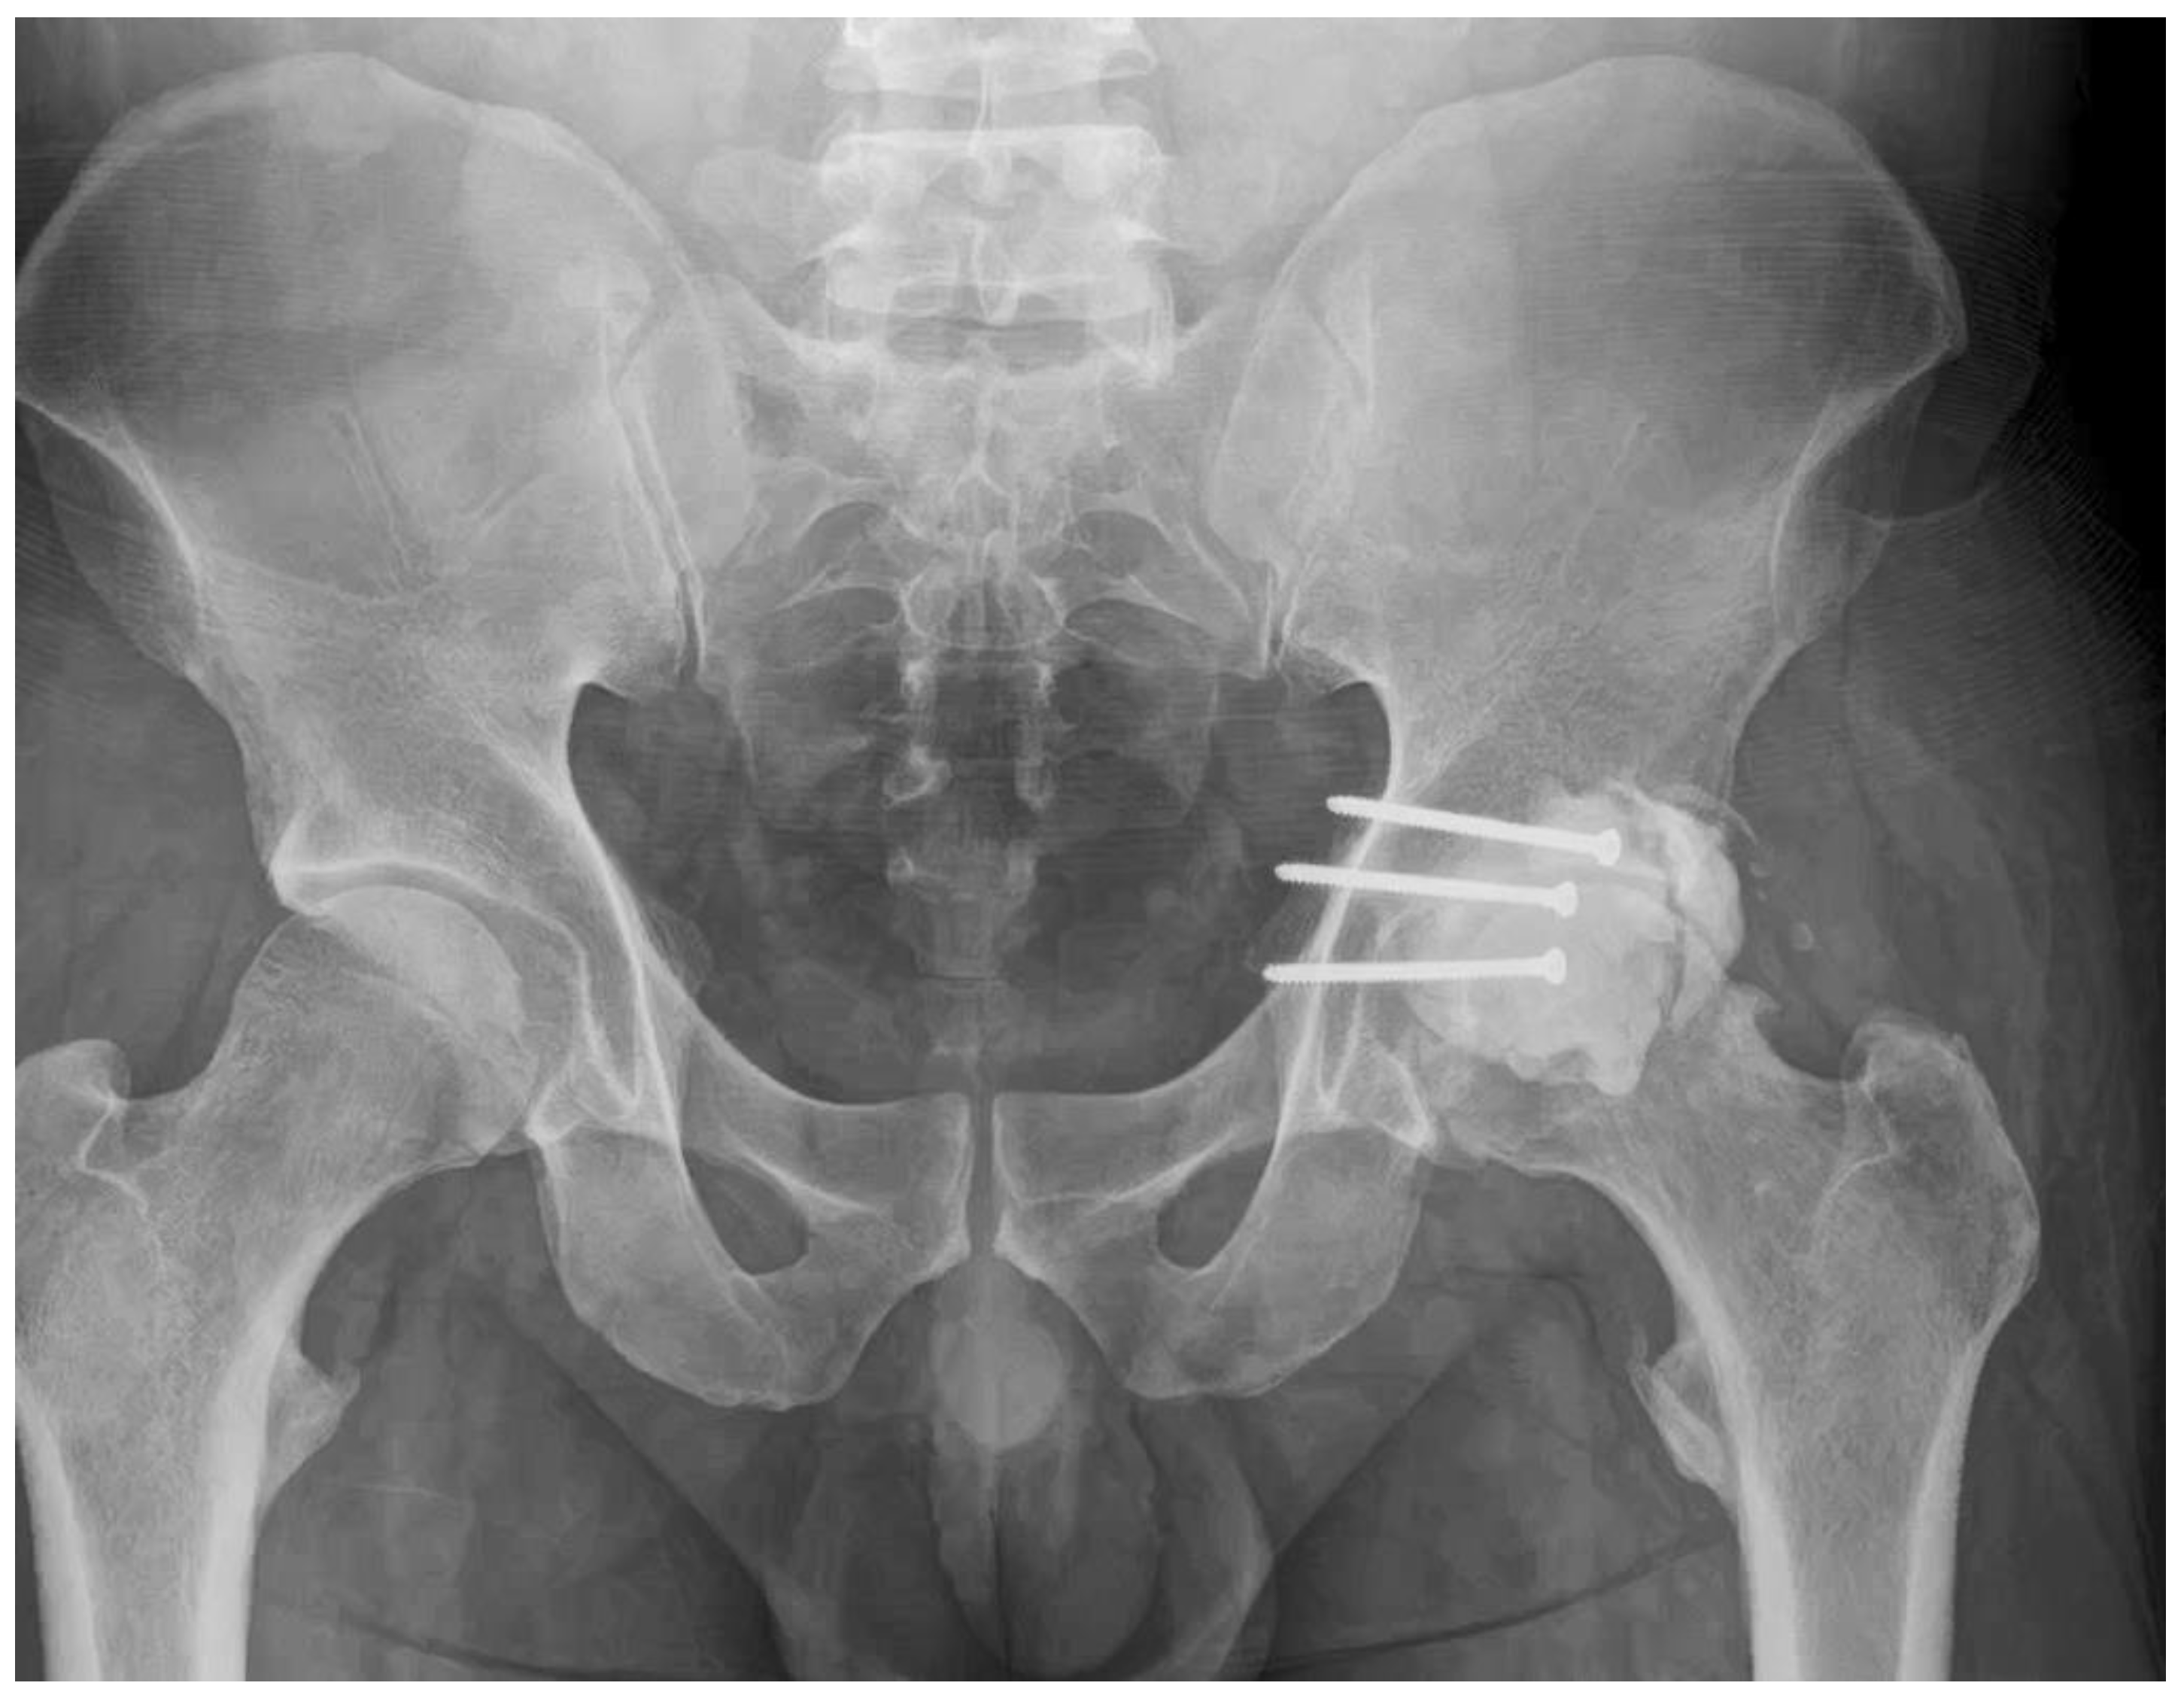

- 21 Months: AP pelvic radiographs showed excellent maintenance of joint space and a stable construct without loosening (Figure 9). The patient’s functional outcome was excellent, reporting no pain during daily activities, with only mild discomfort during deep squatting. The mHHS was 85/100.